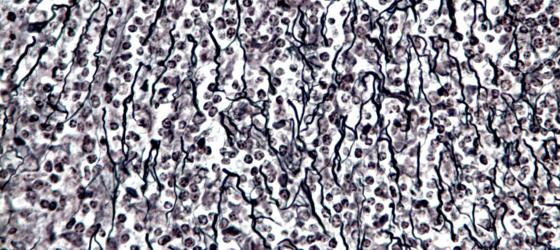

Figure C13. Mouse ovary

Figure C13. Mouse ovary. Reticular connective tissue stained black by silver precipitate. The reticular fibers are defined argyrophilic because of their affinity to silver salts. Bielschowsky X64